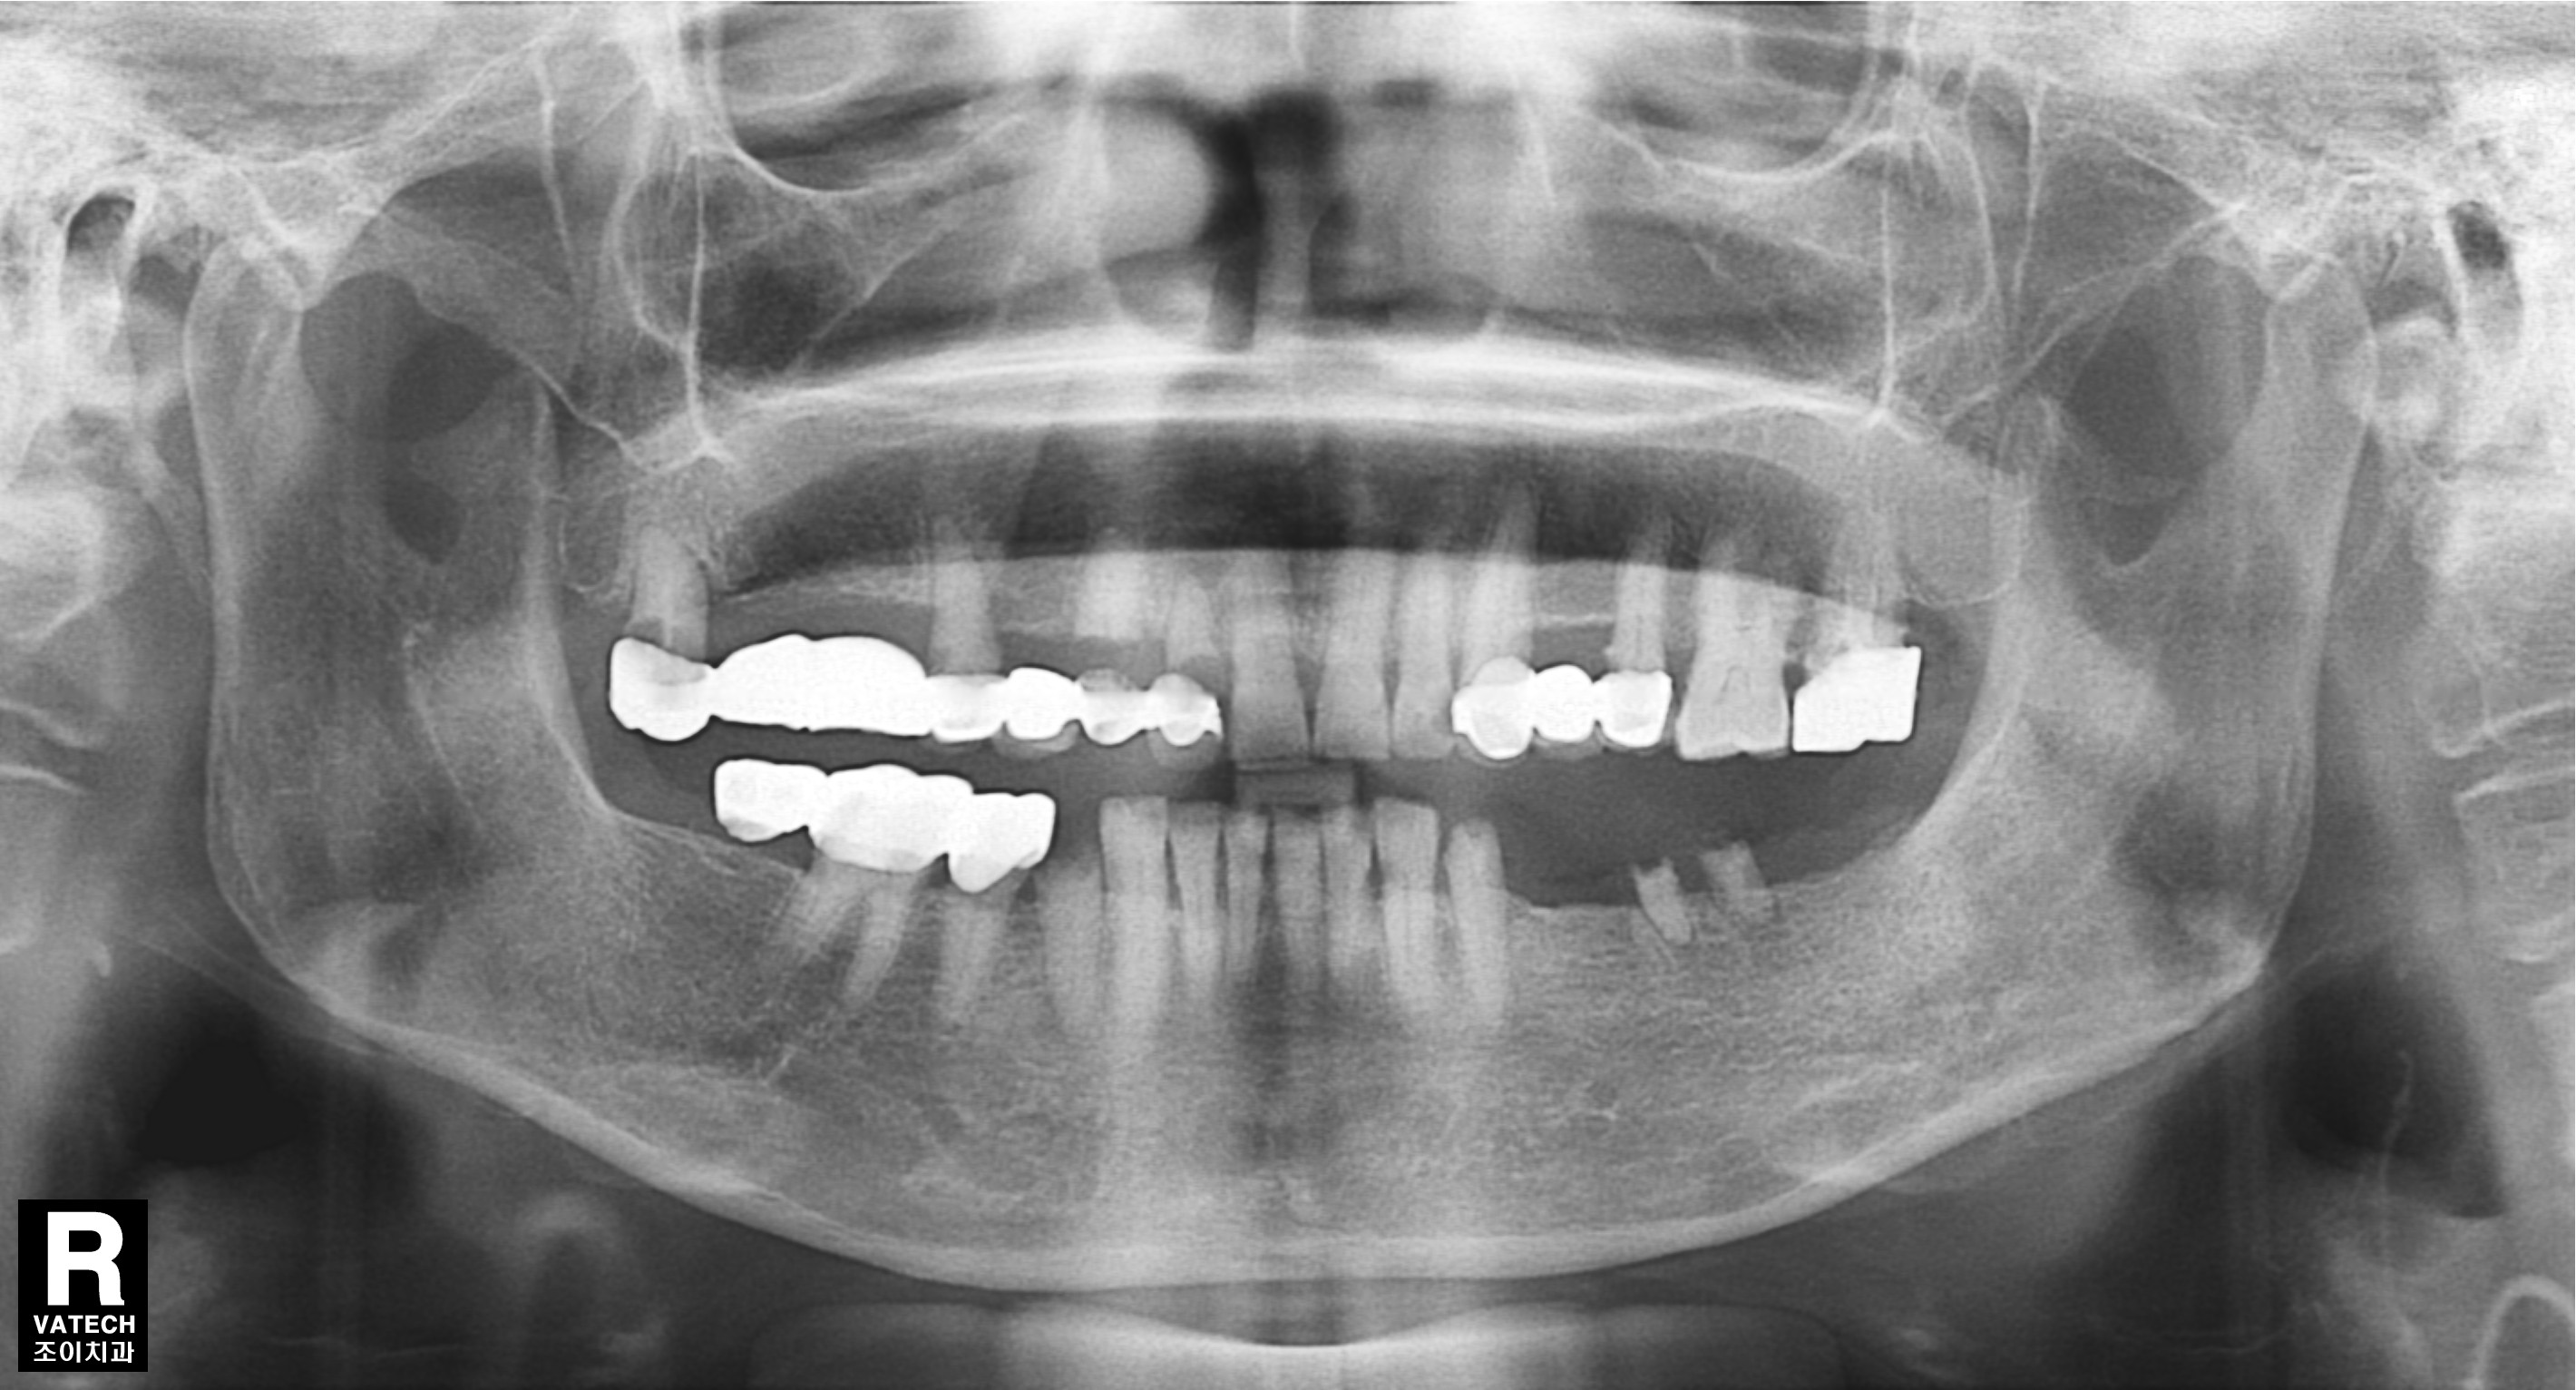

[임플란트] 제목 : 충치로 발치 후

임플란트